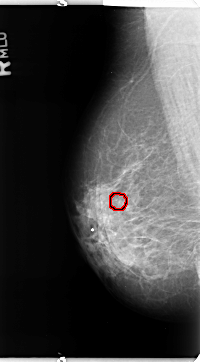

B_3364_1.RIGHT_MLO

FILE: B_3364_1.RIGHT_MLO.OVERLAY

TOTAL_ABNORMALITIES 1

ABNORMALITY 1

LESION_TYPE CALCIFICATION TYPE PLEOMORPHIC DISTRIBUTION CLUSTERED

ASSESSMENT 4

SUBTLETY 3

PATHOLOGY BENIGN

TOTAL_OUTLINES 1

BOUNDARY